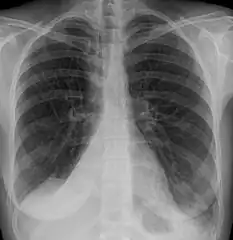

Atelectasis.

Clinically significant atelectasis is generally visible on chest X-ray; findings can include lung opacification and/or loss of lung volume. Post-surgical atelectasis will be bibasal in pattern. Chest CT or bronchoscopy may be necessary if the cause of atelectasis is not clinically apparent. Direct signs of atelectasis include displacement of interlobar fissures and mobile structures within the thorax, overinflation of the unaffected ipsilateral lobe or contralateral lung, and opacification of the collapsed lobe. In addition to clinically significant findings on chest X-rays, patients may present with indirect signs and symptoms such as elevation of the diaphragm, shifting of the trachea, heart and mediastinum; displacement of the hilus and shifting granulomas.[10]